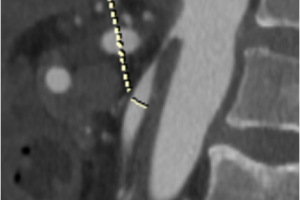

Хирургами центра сосудистой хирургии им. Т.Топпера выполнена уникальная операция по лечению синдрома абдоминальной ишемии у пожилого мужчины с тяжелой сопутствующей патологией. При поступлении пациент предъявлял жалобы на боль в животе, постоянного характера, потерю веса на 27 кг за последние 6 месяцев, отсутствие аппетита. При обследовании выявлены стенозы чревного ствола, верхней брыжеечной артерии и окклюзия нижней брыжеечной артерии, а также трофические изменения в желудке и тяжелое заболевание крови.

Хирурги центра сосудистой хирургии им. Т.Топпера, под руководством Светликова А.В., выполнили операцию по восстановлению кровотока в органах желудочно-кишечного тракта, соответствующую всем Мировым стандартам. Операция была проведена под местной анестезией через кожную пункцию (без разрезов). Боль в животе начала стихать на операционном столе, а полностью прошла в течении часа. На 8 сутки после эндоскопического контроля (ФГДС), на котором была отмечена положительная динамика, пациент был выписан на амбулаторное лечение.